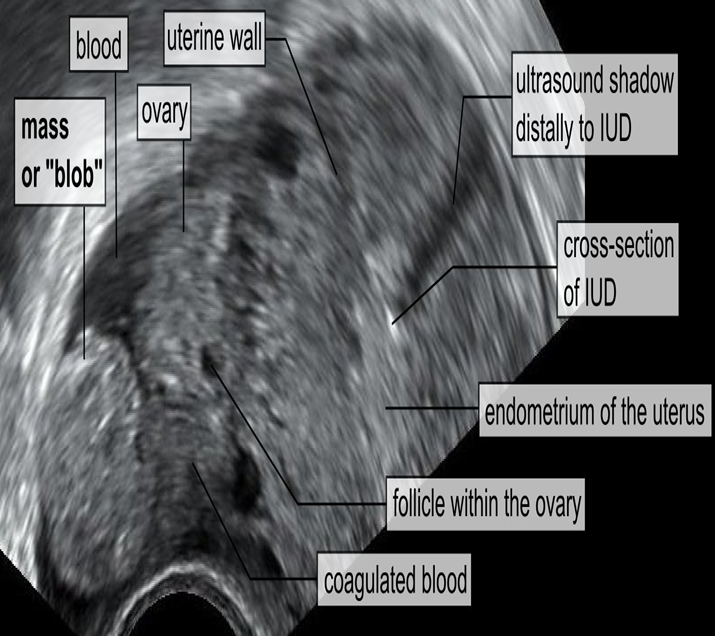

Blob sign of ectopic pregnancy Ultrasound pelvis (transvaginal)

- In the right adnexa, an ectopic pregnancy is visible as a rounded mass (blob sign).

- A small hyperechoic linear structure located centrally within the endometrial cavity represents the visible portion of an IUD